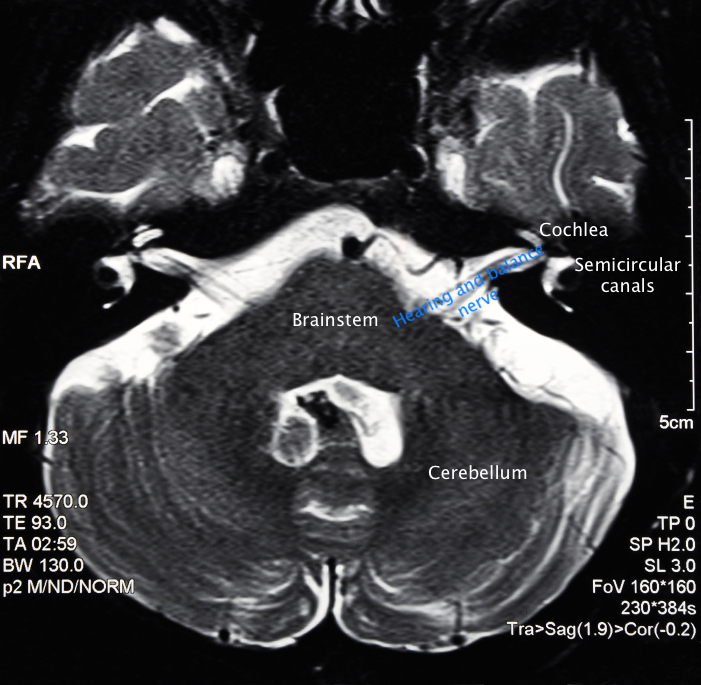

This scan shows a horizontal cross section through the brain at the level where the hearing and balance nerves run from the inner ear to the brain.